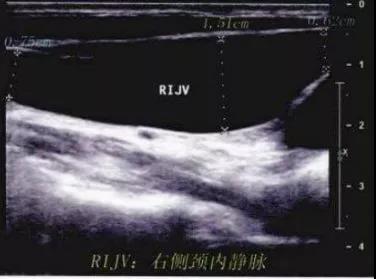

这个病例到底是颈部肺疝还是其他疾病呢?当时首选了超声检查,结果显示为「右侧颈内静脉扩张症」。

超声:B 超及彩色多普勒超声为非侵袭性检查,  诊断率高,重复性强,应作为本病检查之首选。

应用超声检查时,应常规检查双侧颈部静脉。通过彩超可较准确地初步反映肿块的性质、范围及毗邻关系,同时可行血流测定,判断扩张的血管腔内血流状态及是否有附壁血栓等,但当病变延伸至胸腔内或颅腔内时,  该检查受到一定限制。